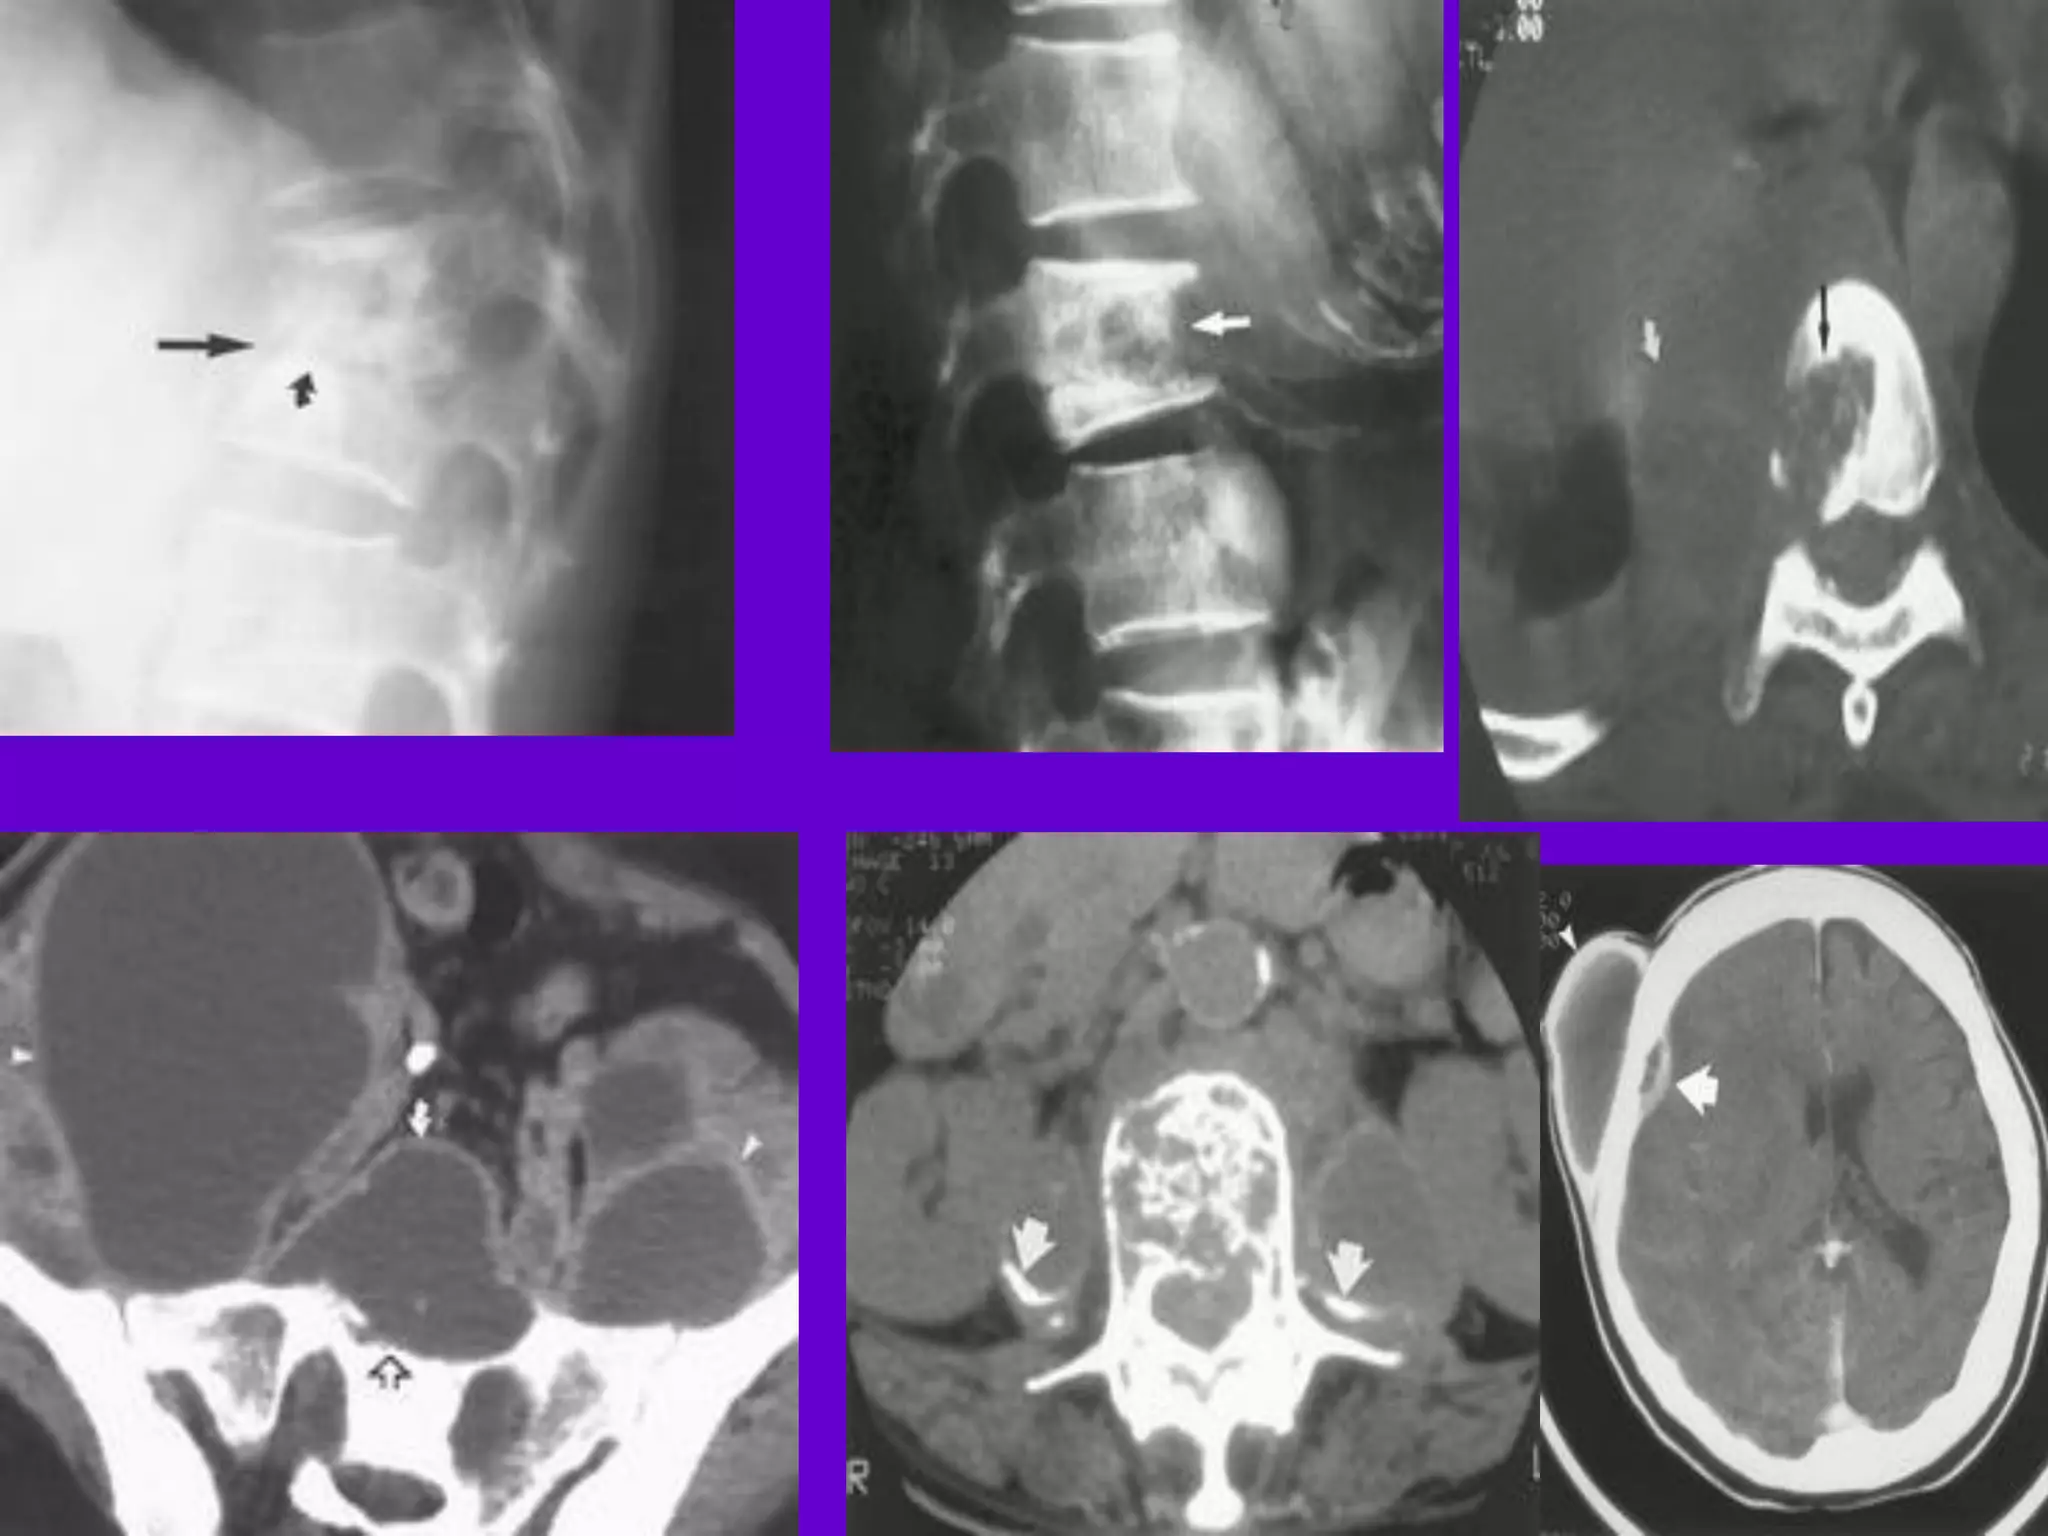

CT Scan and MRI Scan in the

diagnosis of TB

􀂄 The advent of CT and MRI imaging in

the last two

decades has redefined the approach in

analysis of

various diseases including TB.*

􀂄 CT and MRI have shown several

advantages over

conventional radiology in early diagnosis

and follow-up

of TB in different parts of the body.

*Buxi TBS Indian J Pediatr 2002;69:965-972

Pulmonary TB :

Lobar Pneumonia

􀂄

CT is superior than plain CXR in picking

up the

consolidation, atelectasis and the hilar LN

thereby

making the diagnosis easy.

􀂄 MRI reveals some of these changes,

however, CT is

the diagnostic modality of choice in such

cases.

Bronchopneumonia

On CT it is usually B/L and widespread,

not always

symmetrical involvement of lungs.

Hilar and Mediastinal

Lymphadenopathy

CT and MRI depict the hilar and

mediastinal LN

equally well.

􀂄 Calcification in the nodes is however

better seen on

CT.

􀂄 Necrosis is seen as focal areas of low

attenuation on

a CECT.

􀂄 On MRI focal necrosis is seen as areas

of increased

signal intensity on T2W images.

EBTB

HRCT is sensitive in the detection of

early

endobronchial spread of disease.

Miliary TB

􀂄 Earliest form of miliary TB is detectable

on HRCT.

􀂄 Coalescing nodules result into patchy

irregular

opacities and HRCT shows this variation

effectively

and has been described as “snowstorm

appearance”.

􀂄 HRCT shows cavitation, which is not

evident on plain

CXR.

Skeletal TB

Pott’s Disease (vertebral TB)

CT and MRI helps in demonstrating a

small focus of

vertebral body involvement and defining

the extent of

the disease.

􀂄 CT/MRI help to evaluate TB involving

the craniovertebral

junction, sacro-iliac joint and posterior

appendages.

􀂄 They are also helpful in assessment of

spinal canal

encroachment , posterior element

involvement and in

deciding the surgical approach.

GIT TB

Strictures of the small bowel, mucosal

edema and

thickening are well visualized on CT.

􀂄 MRI depicts the para-aortic, aortocaval

and

mesentric lymph nodes effectively.

GUT TB 􀂄

Various patterns of hydronephrosis may

be seen

at MR urography.

􀂄 MRI helps to differentiate macronodular

TB

lesions from the other mass lesions.